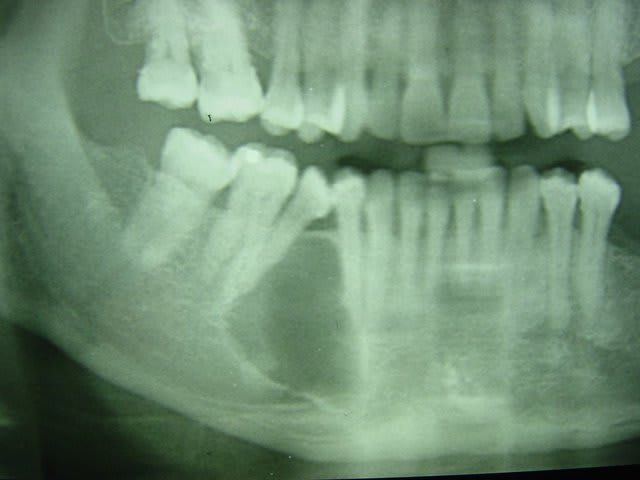

si tu regarde le scanner tu verras que le foramen mentonnier a ete completement repousse au niveau du rebord basilaire par le kyste (desole je ne sai plu quelle numero de photo )

j'ai pu donc realiser un lambeau de pleine epaisseur de 43 a 47 avec incision de decharge en mesial de 43 puis arrive au niveau du rebor basilaire j'ai disseque en epaisseur partiel.